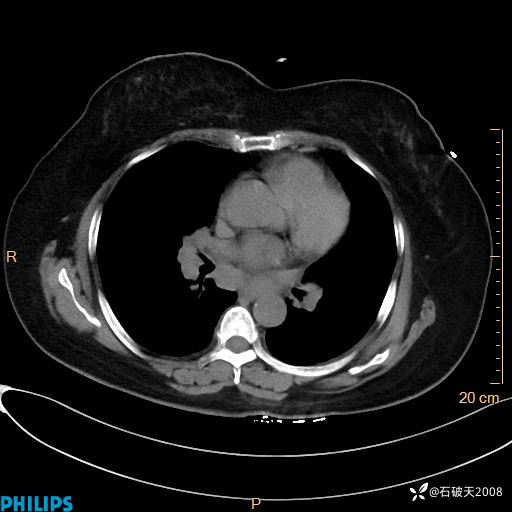

肺窗

纵隔窗